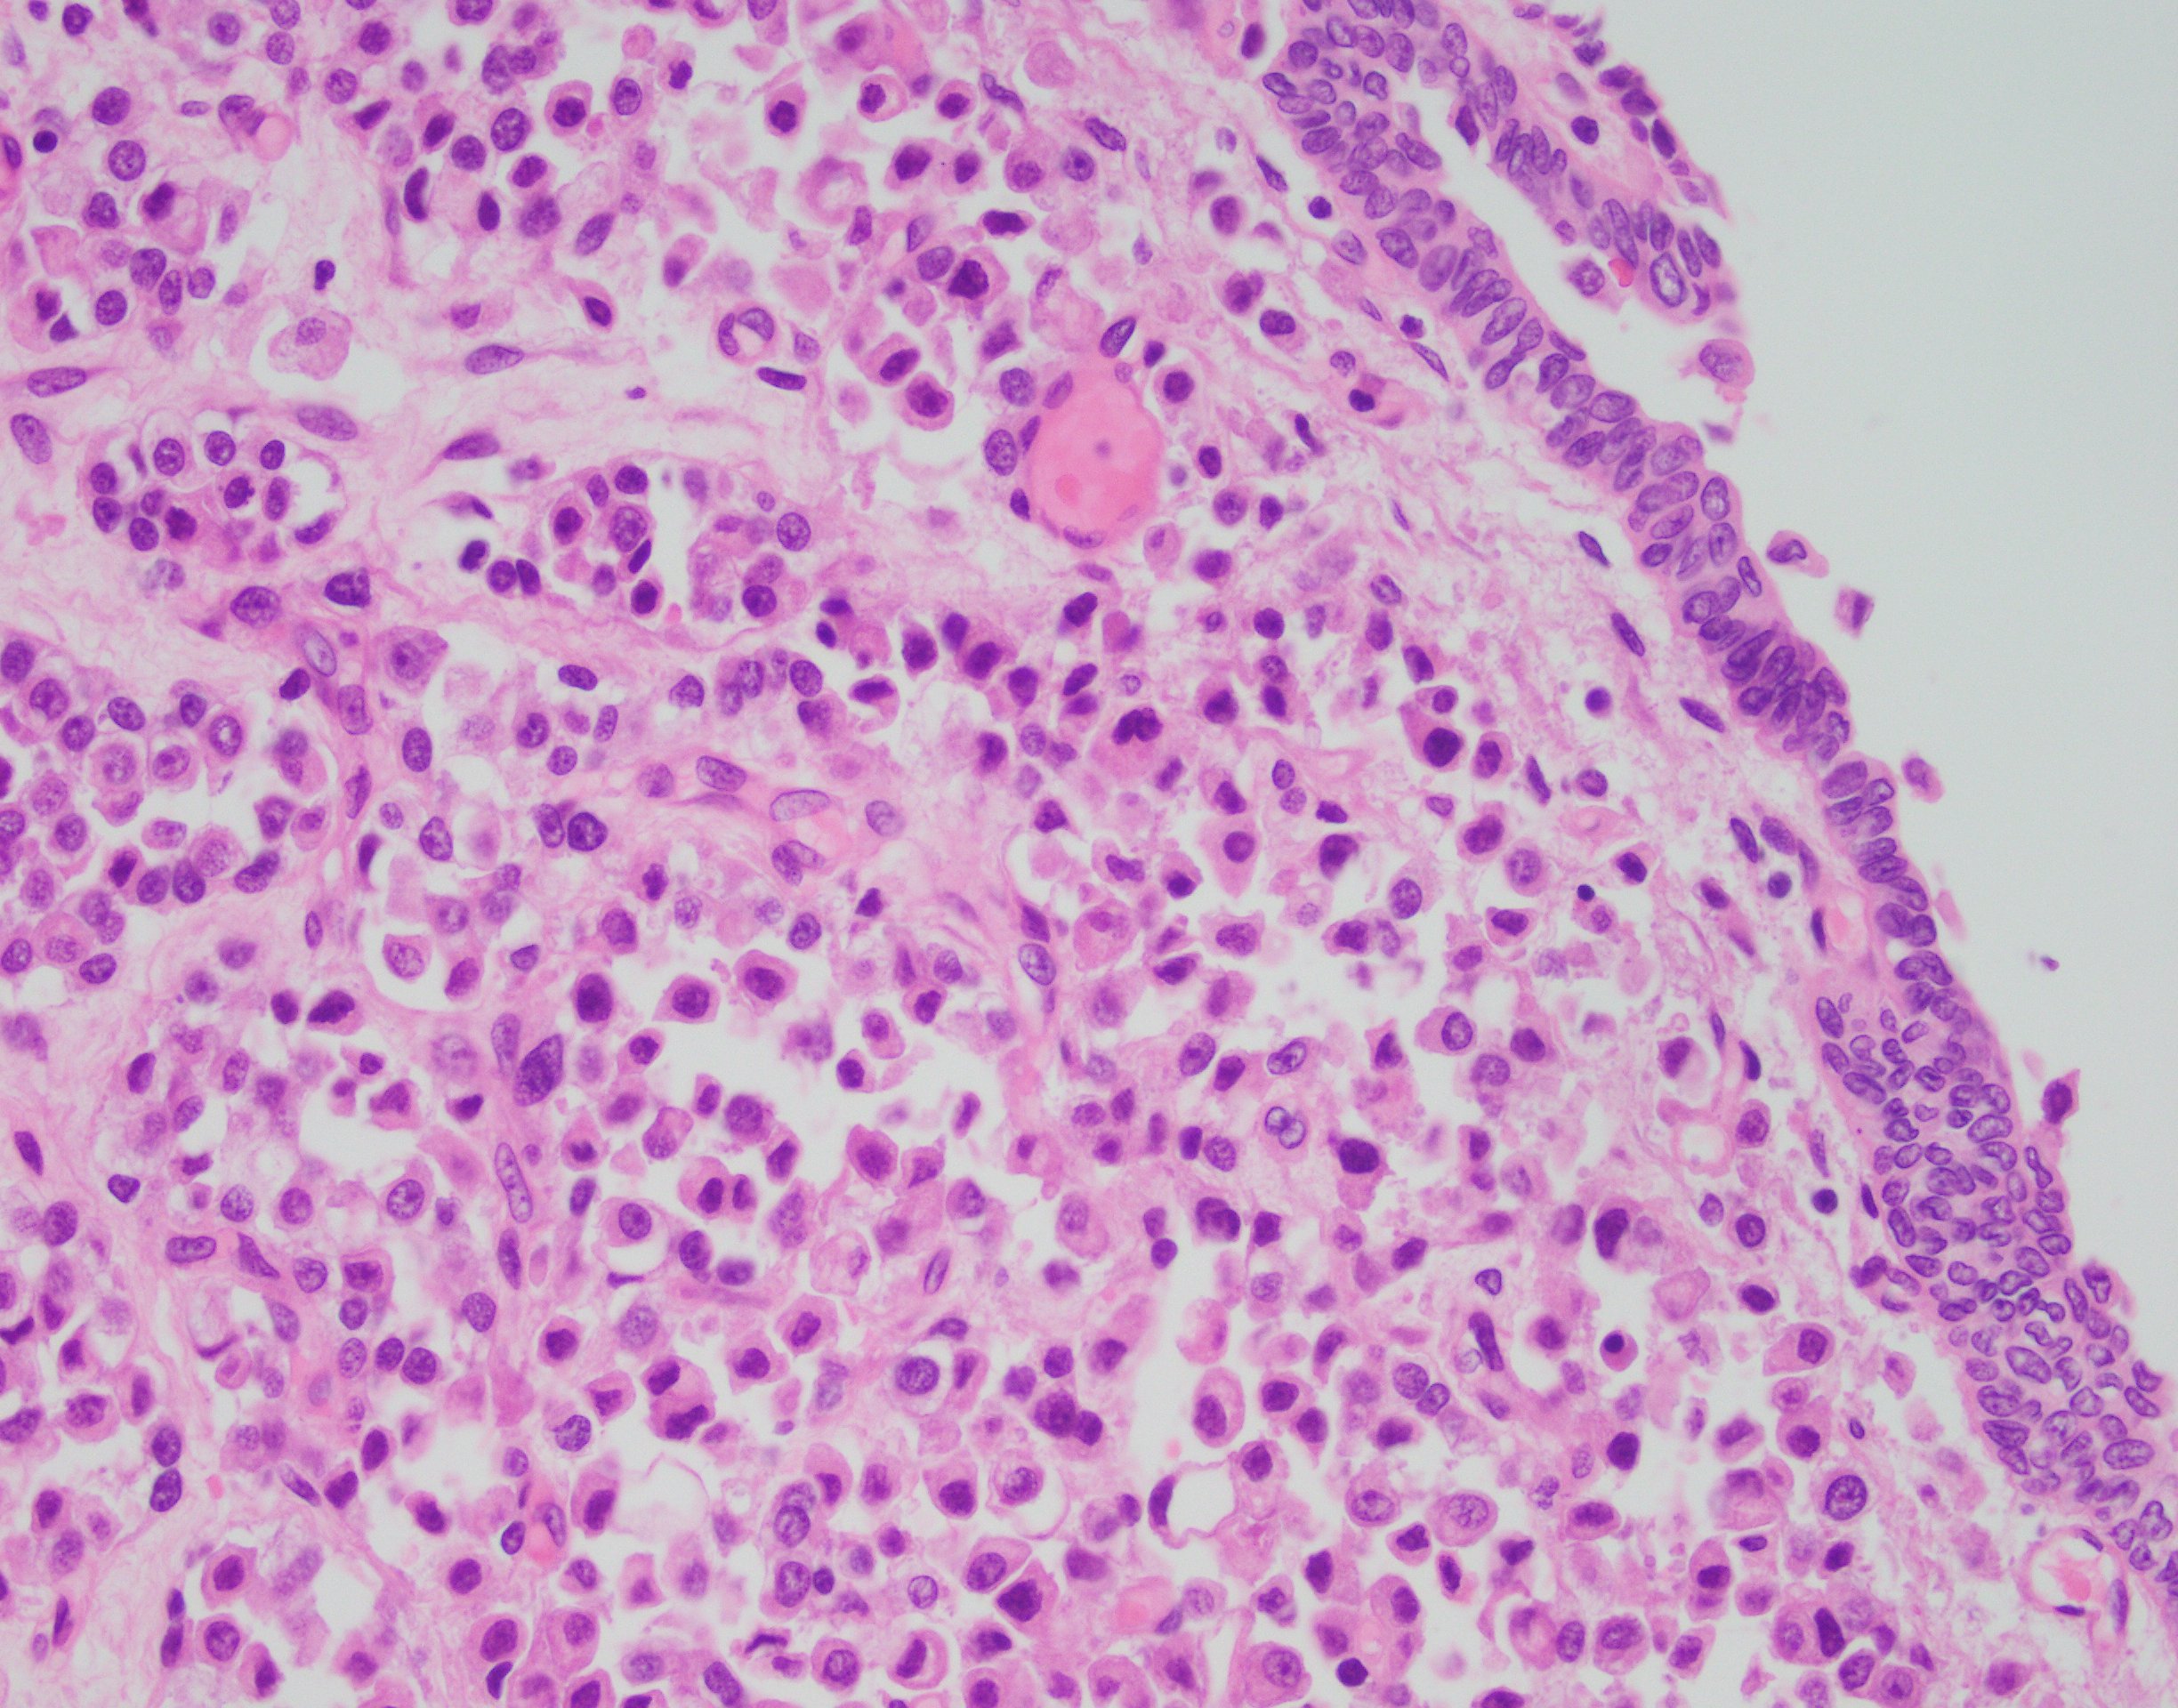

The findings in this case show a diffuse, infiltrative, and discohesive tumor extending into the perivesical adipose tissue. There is extensive perineural and lymphovascular invasion. Focal areas show urothelial carcinoma in situ. Tumor cells have eosinophilic cytoplasm, and nuclei are eccentrically located with focal signet ring cell features. Staining with p63 and GATA3 was performed and shows positivity in both stains.

These features are all consistent with the plasmacytoid variant of urothelial carcinoma. Typically, this variant grows in a linitis plastica-like manner. Tumor infiltration is diffuse, in single cells or cords. Characteristically, tumor cells exhibit eccentric nuclei and/or signet ring cell morphology. Of note, these tumors stain similar to usual urothelial carcinomas, but also strongly express CD138 and lose E-cadherin expression. Most tumors are locally advanced at the time of diagnosis and are highly aggressive.